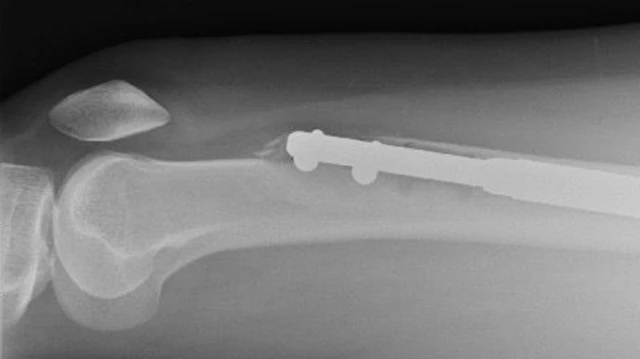

यहां ऑर्थोपेडिक सर्जन थे जीन-मार्क गुइशेट, जो हड्डी लंबा करने के विशेषज्ञ थे. उन्होंने अपना एक उपकरण- गुइशेट नेल भी इजाद किया था.

इस प्रक्रिया में थोड़ा दर्द होता ही है क्योंकि पैर की हड्डी को दो हिस्सों में तोड़कर उनके बीच मेटल की रॉड लगाई जाती है.

धीरे-धीरे दोनों हिस्सों के बीच लगे मेटल के इस रॉड की लंबाई बढ़ाई जाती है, जिससे मरीज़ की लंबाई बढ़े.

दूसरे दिन जब स्कैन हुआ तो इलेन का डर सही साबित हुआ. उनके बाएं पैर में लगा नेल (कील) हड्डी को चीरता हुआ बाहर निकल आया था. ये फीमर (पैर के ऊपरी हिस्से की हड्डी) को तोड़कर बाहर आ गया था. फीमर शरीर की सबसे मज़बूत हड्डी होती है.